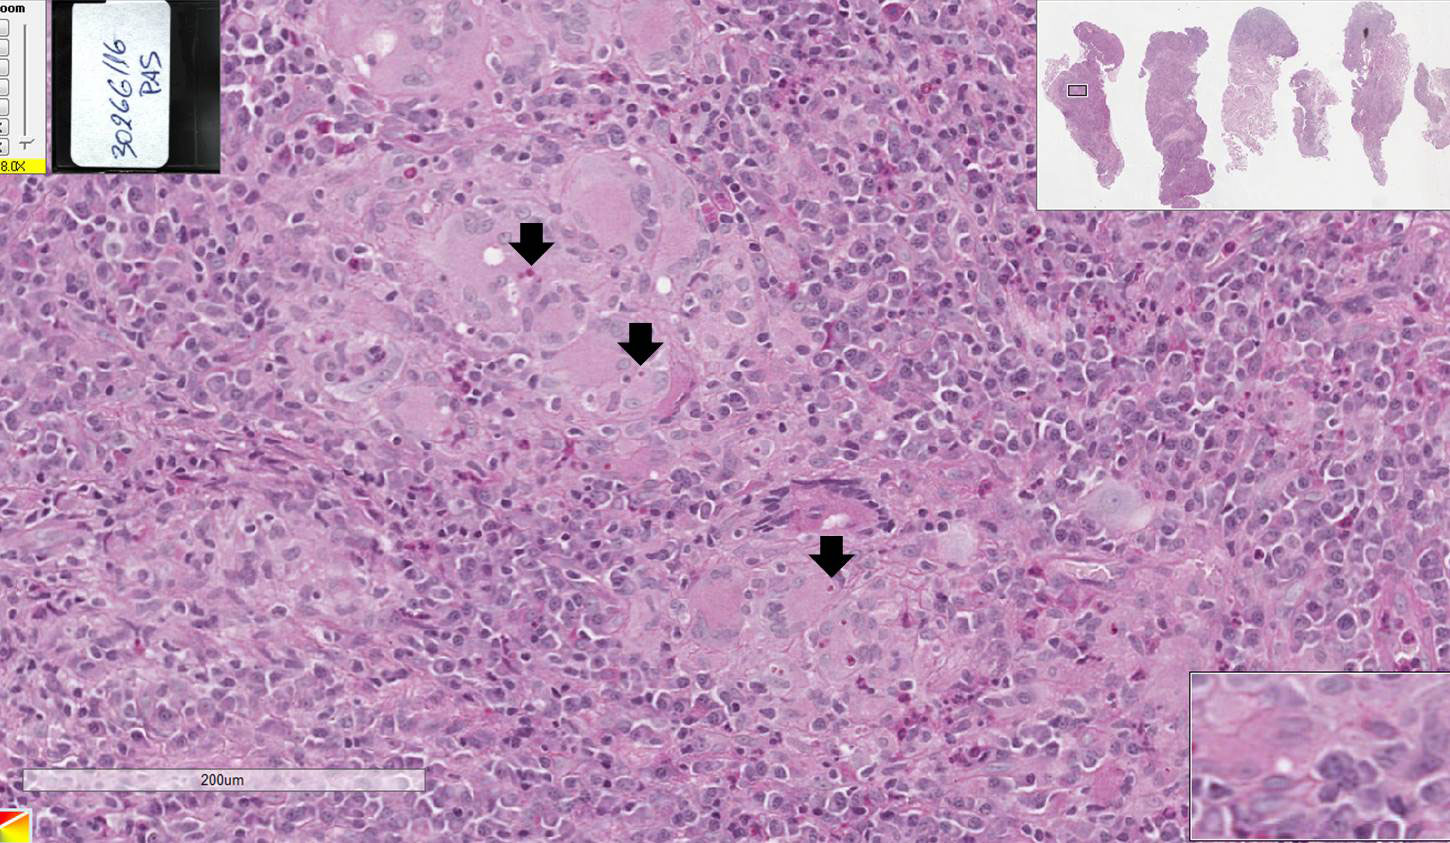

Infecção fúngica profunda, ocasionada pelo organismo Paracoccidioides brasiliensis.

Fragmento de mucosa revestido por tecido epitelial estratificado pavimentoso ceratinizado, apresentando hiperplasia pseudoepiteliomatosa (sensação de que o epitélio “invade” o tecido conjuntivo) e áreas de micro abcessos (pequenas coleções de neutrófilos e piócitos superficiais). No tecido conjuntivo subjacente, observa-se a formação de granulomas (circunscrito pelo tracejado) que apresentam externamente fibroplasia (setas pretas), seguida por um colar de linfócitos (asterisco vermelho), e mais centralmente observam-se um aglomerado de macrófagos epitelióides (asterisco amarelo - núcleo claro e alongado e as células podem apresentar um arranjo em paliçada ou justapostas umas às outras). Entremeados as células do granuloma observam-se células gigantes do tipo Langhans. Em algumas áreas, principalmente no interior das células gigantes, é possível visualizar os fungos que se apresentam como um espaço negativo (branco) e forma geométrica redonda (asterisco verde).

Observar os granulomas compostos por um aglomerado de macrófagos epitelióides, colar de linfócitos e fibroplasia externa assim como a presença de células gigantes fagocitando os fungos. Os microabcessos e a hiperplasia pseudoepiteliomatosa são sugestivos, mas não específicos desta doença.

Paracoccidiodomicose